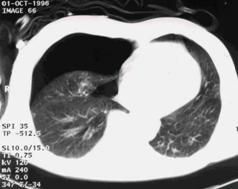

Contuzie pulmonara stanga Contuzie pulmonara dreapta

Contuzie pulmonara dreapta.Imagine CT